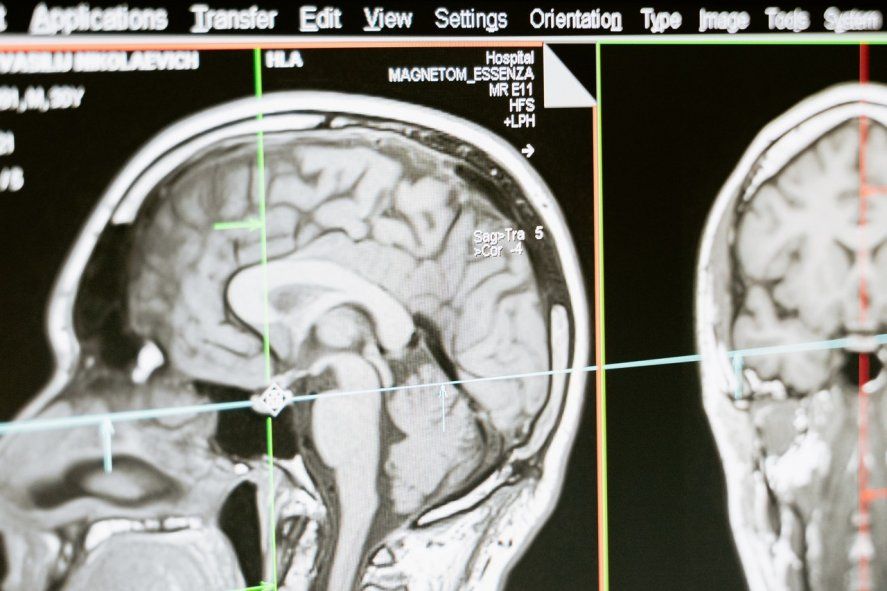

¿Cómo se diagnostica la ELA?

De acuerdo a la Asociación ELA Argentina, la enfermedad puede ser extremadamente difícil de diagnosticar por varias razones:

- No existe un examen específico para probar que alguien tiene ELA, lo cual significa que el diagnóstico requiere la eliminación de otras enfermedades potenciales.